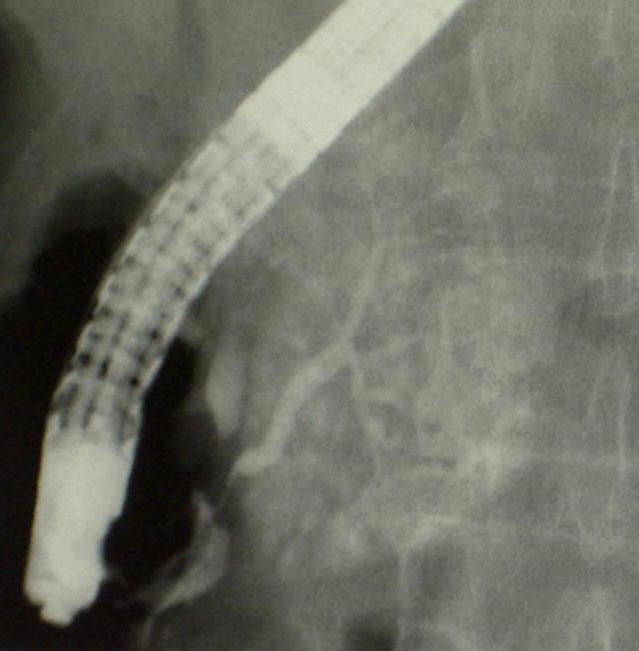

14.1.1.7. Percutaneous transhepatic cholangiography (PTC)

The percutaneous contrast filling of the biliary ducts can be necessary if no reassuring diagnosis was made by US, CT or MRI scans, or the ERCP implementation was unsuccessful due to a technical obstacle (Billroth II. gastric resection, choledochojejunostomy), or the canulation of the papilla of Vater was technically failure. PTC can be only performed in case of appropriate bleeding or coagulation status. (Figure 9) .

Figure 9: PTC (Percutaneous transhepatic cholangiography)

Significant amount of free abdominal fluid is also a relative contraindication. In the course of PTC, the liver punction is usually performed in the 9th or 10th rib spaces under fluoroscopic guidance using a 22 G Chiba needle. The punction should be guided towards the liver hilum. US guidance is helpful in the easier puncture of dilated or even peripherially located biliary ducts. The entire biliary system can be filled through this puncture. Following the diagnostic biliary duct contrast administration – after a previous consultation – bridging of the detected biliary stenosis can be performed (PTC-PTD, biliary duct stenting). Moreover, percutaneous stone extraction can be carried out if necessary.